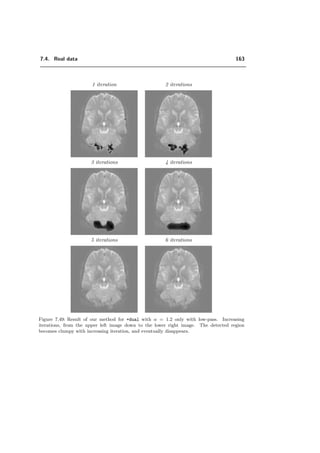

7.4 Real data . . . . . . . . . . . . . . . . . . . . . . . . . . . . . . . . . . . . 151

7.4.1 Image acquisition . . . . . . . . . . . . . . . . . . . . . . . . . . . . 151

7.4.2 Relation between our algorithm and SPM . . . . . . . . . . . . . . . 153

7.4.3 Control of E1−error . . . . . . . . . . . . . . . . . . . . . . . . . . 158